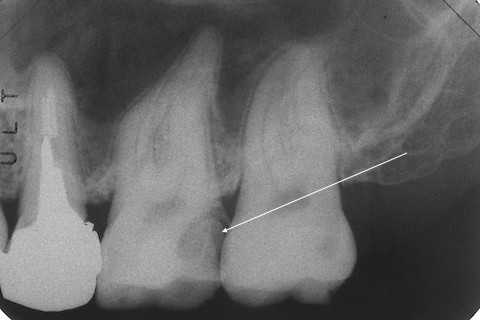

今日の抜歯再植術シリーズ1.2

50代女性、左下6、歯根破折ここのコメント欄にもあるように、患者目線でのきちんとした治療ができない理由だが、この100年以上にわたって強固な診療システムが確立していて、このシステムから逸脱することが非常に困難だからだと思う。歯科医療は分業体制で成り立っており、ま、どこの世界でも同じではあるが、例えば、よくある治療の流れは1、神経を取って型取りする2、歯科技工士に冠の作製を依頼する3、納品された冠を口腔内にセットするだが、この流れからドロップアウトするといきなり経済的に、もしくは肉体的に行き詰る。僕は歯科技工士上がりなので、1から3まで全部できはするが、実際にやると寝る時間が無くなり、倒れる。2年は頑張ったが。では無理のない範囲でゆっくりやれば良いではないかと思われるかもしれないが、それでは食べていけないだけではなく、患者をさばけない。患者単価が非常に高くなってしまうからだ。では、僕はどうなのかといえば?歯を削ると問題が生じるのだから、削らない。これは守っている。この症例も安易に削って被せたばかりに問題が生じたと言えるわけなのだが、削らないとすれば、どうやって食べていくか、このブログ記事がその答えでもあるのだ。しかし現実は厳しい。この世は修行だと思って、とことんがんばるしかないと思わないとやっていけないだろう。しかも超絶技巧が必要だ。そんな歯科医師がいるのか?と言われるといるわけがない。誰でも楽をしたい、しかしお金だけは欲しい。今だけ、金だけ、自分だけだ。読者の皆さんはそうではないですか?・・今日はレントゲン写真を3つ挙げておこう。破折した直後。破折線が明瞭に見えると思う。その3ヶ月後、歯根はバラバラになっている。抜歯再植後つづく

今日の抜歯再植術シリーズ1.1

60代男性、左下7、歯根破折あっちのブログはまだ復旧できそうもないので、こっちが続きます。この方、よく噛んで食べると健康を維持できるというお考えの方ではないかと思う。ま、確かにそうなんだが、60も過ぎると歯の耐用年数が来てしまう。歯の機械強度が落ちてくる。歯は劣化する一方なのだ。特に神経を取ってある歯は弱い。最初から神経を取らないようにするべきなんだが、そうではなくても人生100年を見据えるのなら、歯には過度な力をかけずに大切に使うべきだ。近心根は砕けていて使えるパーツが少ない。遠心根にもクラックが入っていて離断寸前だった。さすがに再建しても生着は厳しいかと思ったが、諦めないでやってみようと思った。歯根表面の40%近くが◯ーパー◯ンドになってしまったが、その上にもセメント質も歯根膜も再生することもある。確か猿での実験で確認されたという論文を見たことがある。人間でも当然あると思う。ただ、強固な歯牙固定が必要になるが、隣在歯にはセラミックインレーが入っており、接着が強固にはできないのが問題だ。最初はレントゲン写真でのbefore/afterだが、さすがに厳しいと思うだろう。beforeafterでは時系列でどうぞ